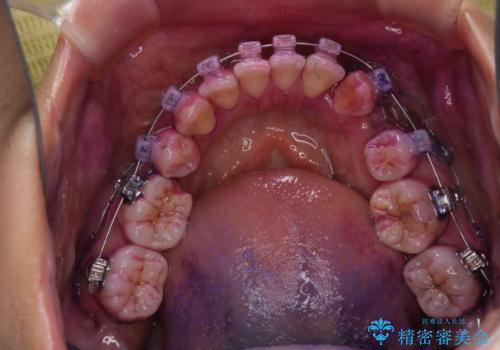

- ワイヤー矯正中に、口臭や汚れが気になり綺麗にクリーニングしたいとのことでした。染め出しをしての歯磨き指導とPMTC60分コースを行いました。

ワイヤー矯正中はブラッシングが難しくなるため、磨き残しが多くなることがあります。

ご自身でのブラッシングケアでは、歯周ポケットの中に歯ブラシの毛先が届くのはわずか2ミリ程です。軽度の歯周炎の場合でも歯周ポケットは3ミリほどあります。歯茎の中に長く汚れが溜まると、歯石や細菌などがつき、口臭の原因にもなります。

適切な道具を使って、適切なブラッシング方法を習得することで、磨き残しを減らすことができます。

また、矯正で歯の移動があると今までなかったところに隙間が出てきたり、ガタつきが解消されてきたりすることで、お口の中の環境が変わります。

矯正治療中も清潔な口腔内を保つことは、とても大切です。そのため、定期的に専門的な機械・材料を使用したProfessinnalcleaning(pmtc)を行うことがおススメです。